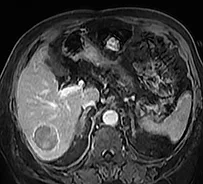

Tout d’abord une augmentation paradoxale de la taille de la tumeur peut être observée dans la phase initiale en raison de la nécrose et de l’œdème, elle est observée jusqu’à 36 % des lésions durant le 1er mois. Par conséquent, l’évaluation de la réponse tumorale doit être effectuée après 3 mois (98). La décroissance en taille de la lésion est très lente, avec une réponse complète et des critères d’amélioration qui augmentent avec le temps : dans l’étude de Lee et al., la réduction de la taille de la tumeur est de 2 % à 1 mois, 14 % à 3 mois, et 28 % à 6 mois (99). Bien que la diminution de la taille de la tumeur soit rassurante, l’absence d’augmentation dans le temps est un signe positif, et peut être considéré comme le reflet d’une réponse clinique, car l’histoire naturelle de la tumeur est la poursuite de la croissance tumorale…

Il est préférable d’utiliser les critères mRecist pour juger de l’efficacité du traitement (100), mais les variations du réhaussement tumoral, la diminution de l’hypervascularisation peuvent se faire attendre. Les données de Lee et al. montrent une amélioration selon mRecist dans 31 % des cas à 1 mois, 50 % à 3 mois et 59 % à 6 mois. Par conséquent, il faut attendre jusqu’à 3-6 mois avant de prendre la décision de retraiter, le meilleur signe de progression étant l’apparition de nouvelles lésions péritumorales ou à distance dans le foie.

La confrontation de l’analyse histologique d’explants après RE a montré que les 49 % de patients pour lesquels l’imagerie avait conclu à une réponse partielle présentaient en fait une nécrose complète histologique dans 78 % des cas, ce qui montre bien la difficulté de l’interprétation radiologique de l’imagerie de surveillance (101). Toujours dans cette étude, la présence d’un réhaussement annulaire périphérique, correspondant au tissu de granulation entourant la nécrose, était un signe de réponse positive puisque 93 % de ces lésions avec réhaussement annulaire présentaient une nécrose complète.

| Contrôle par IRM (acquisition en pondération T1 à la phase artérielle et portale) à 1 an du traitement par radiothérapie sélective interne par Therasphères dans l’artère hépatique gauche avec une dose à la tumeur de 370Gy. A noter la prise de contraste annulaire périphérique séquellaire de la lésion involuée. | |